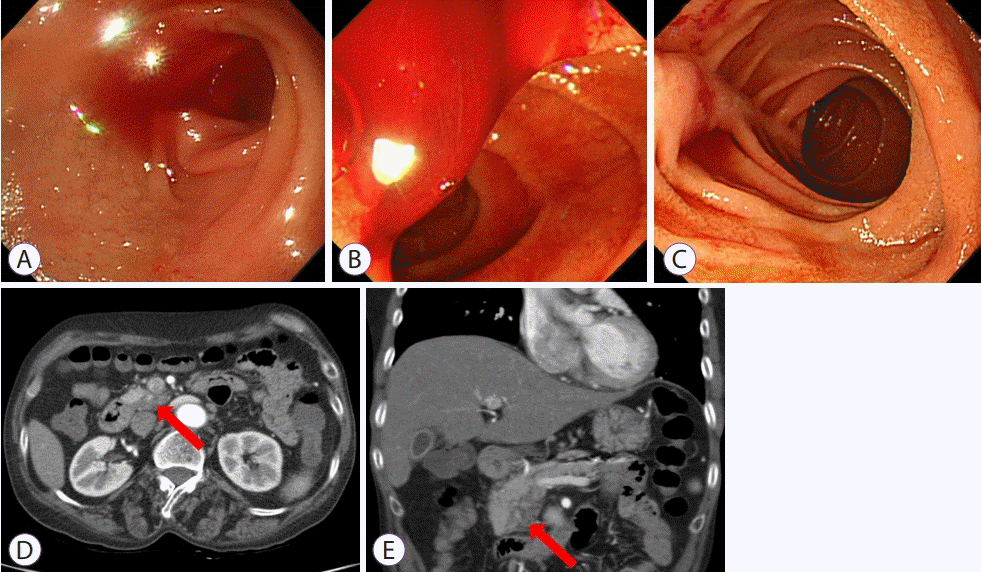

A 57-year-old woman was admitted to the hospital with melena and dyspnea. Her initial hemoglobin level was 6.5 g/dL. She had a history of acute pancreatitis with splenic pseudoaneurysm, which had been treated with angiographic coil embolization 1 year previously. After transfusion of several packs of red blood cells and tests for anemia, she underwent endoscopic examination. The colonoscopy findings were normal. Gastroscopic examination revealed blood in the second and third portions of the duodenum and suspicious active bleeding from the orifice of the ampulla of Vater (Fig. 1A-C). Because the bleeding focus was not clear, computer tomography (CT) scans and capsule endoscopy were performed. There was no evidence of bleeding in the small bowel during capsule endoscopy; however, CT scans revealed parenchymal swelling and an early enhancing lesion in the pancreatic uncinate process (Fig. 1D, E). What is the most likely diagnosis?

Given the focal early enhancing lesion in the pancreatic uncinate process, which was thought to reflect recent bleeding, hemosuccus pancreaticus was suspected. After CT scans, the patient underwent angiography but failed to receive additional embolization due to the previous coil (Fig. 2A). She finally underwent laparoscopic distal pancreatectomy because of the recurrent bleeding; the surgical specimen revealed a pseudoaneurysm at the splenic hilum (Fig. 2B).